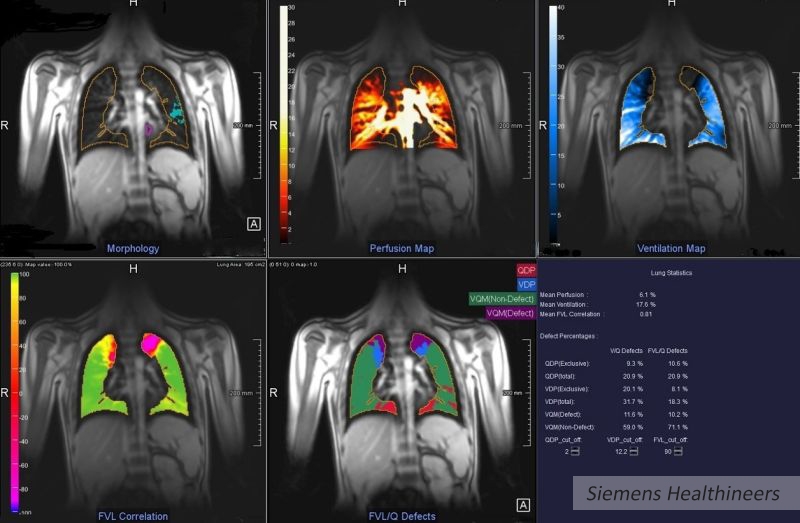

Czy informacje na temat perfuzji i wentylacji (wartości podawane przez prototyp naukowy firmy Siemens MR Lung) płuc, dzieci chorych na mukowiscydozę, mogłyby potencjalnie zwiększyć ilość informacji o stanie ich zdrowia? Czy informacje te można byłoby uznać za pomocne w przypadku braku możliwości podania środka kontrastowego lub gazów hiperpolaryzowanych?

Projekt przewiduje wykorzystanie algorytmów zapewniających automatyczną segmentację płuc do obliczania perfuzji i wentylacji na podstawie standardowych sekwencji MR. Zastosowanie nowych sekwencji nie wpływa na wydłużenie czasu badania, a potencjalnie pozwala na uzyskanie dodatkowych informacji o funkcjonalnych zaburzeniach płuc. W ramach współpracy naukowo-badawczej sprawdzane będą możliwości korzystania z tego rozwiązania, jako alternatywy dla stosowania środków kontrastowych i gazów medycznych w diagnostyce i leczeniu dzieci.